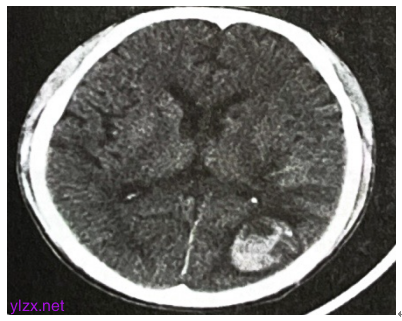

双侧髂静脉、股静脉、胭静脉、胫前静脉及胫后静脉未见明显异常。颅脑CT:左侧枕叶出血,左顶叶小灶性出血可能(图3)。

图3 颅脑CT

11月27日患者出现持续性头部胀痛,急查颅脑CT示左顶叶小灶性出血可能,给予甘油果糖脱水等处理,16时左右患者出现神志改变、双侧眼球上翻、口吐白沫、呕吐胃内容物等症状,继续予以脱水处理后患者短时间神志转清,仍间断抽搐。